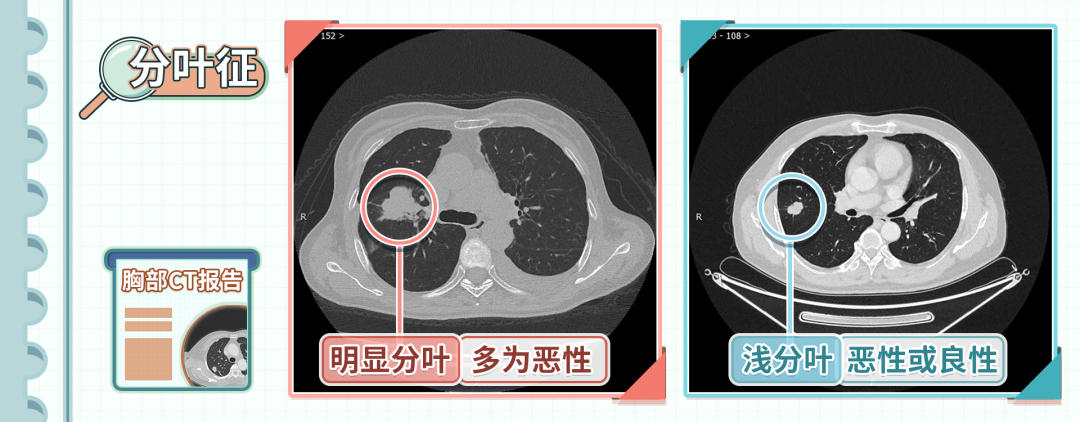

2、分叶征

分叶征是指结节边缘不光滑,呈分叶状。

主要是由于肿瘤组织向各方向生长不均匀造成的,也可能是由于气管、血管和叶间裂等框架结构阻挡造成的。

出现明显的分叶,恶性的可能性特别高,是肺癌比较明显的征象;浅分叶可以是恶性的,也可以是一些良性病变,比如结核,要进行鉴别。